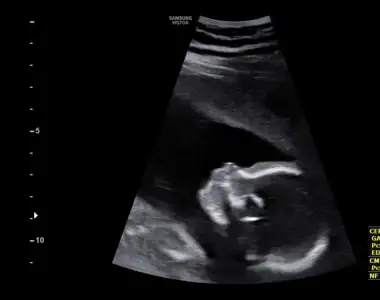

Ay ben hiç dikkat etmedim dur ultrason kağıdıma bakayim sanki yuvarlak benim oğlanın kiBenimki de yuvarlak değil elips gibiaynen bence de böyle iyi. Ben zaten çok severim hafif arkaya bombeli kafaları